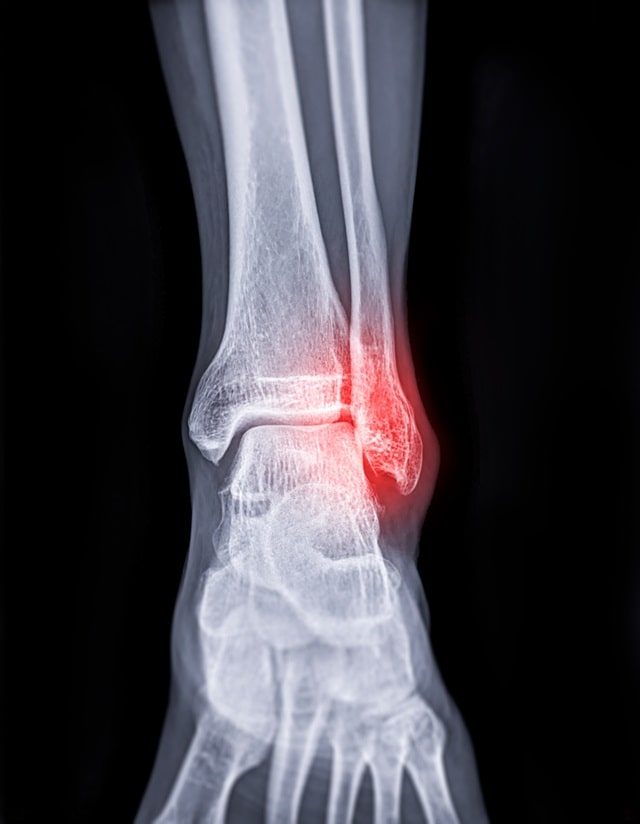

- X-ray 촬영: 발목 뼈에 골절이 있는지 확인하기 위해 X-ray 촬영을 시행할 수 있습니다. 이는 뼈 손상 여부를 확인하는 데 가장 기본적인 검사입니다.